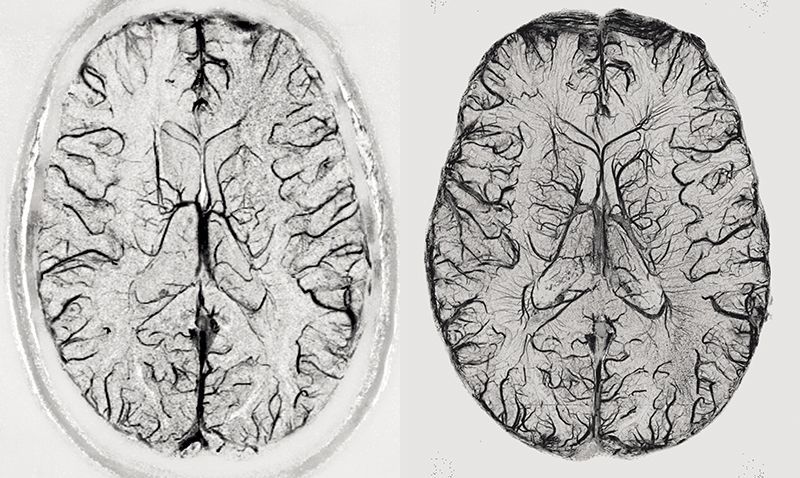

图 | 使用3T(左)和9.4T(右)核磁共振扫描仪的大脑成像对比(来源:Rolf Pohmann/Max-Planck-Institute for Biological Cybernetics)